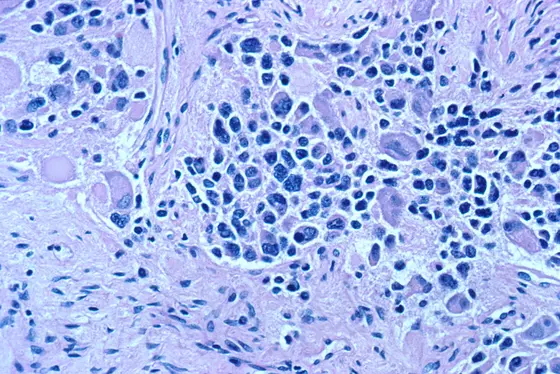

Neuroblastomas are pediatric tumors originating from cells of the embryonic nervous system. The disease can take extremely varying clinical courses, ranging from spontaneous regression to fatal outcome. The most aggressive tumors are characterized by up to 100-fold amplification of the MYCN oncogene.

For a couple of years now, clinicians have been fighting various cancers using substances inhibiting the activity of HDAC enzymes, or HDAC inhibitors. In the culture dish and in tumor-bearing mice, these drugs are also effective against neuroblastoma. Led by Dr. Hedwig Deubzer, a group of scientists from the German Cancer Research Center (Deutsches Krebsforschungszentrum, DKFZ) and Heidelberg University Hospital have studied the exact cellular structures of neuroblastoma cells affected by these drugs. “Only about 20 to 40 percent of high-risk neuroblastoma patients survive the disease in the long term. Therefore, we urgently need to find better treatments for this aggressive form of the disease. To increase the efficacy of drugs, it is extremely important to understand where exactly they work in the cell," says Deubzer, a pediatrician.